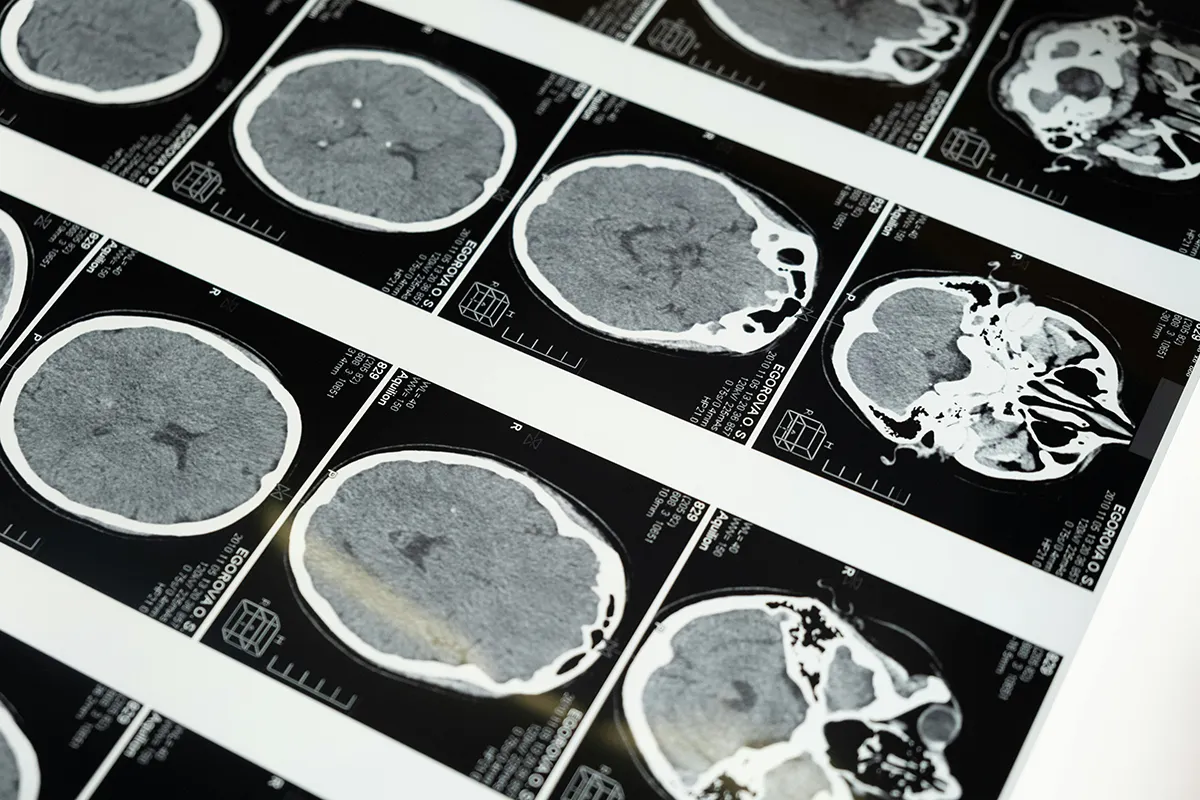

Aneurisma Cerebral: Una Amenaza Silenciosa y Cómo la Oxigenoterapia Hiperbárica Puede Ayudar

El aneurisma cerebral es una afección grave que afecta aproximadamente al 3 % de la población mundial. Aunque muchos pasan